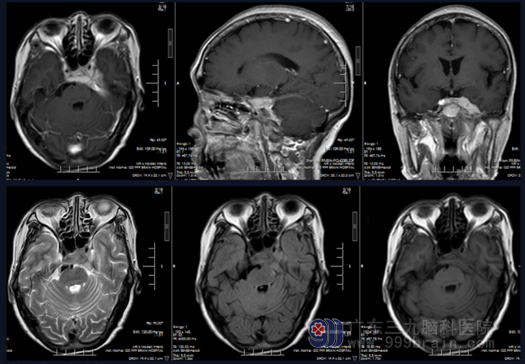

头颅 MR 示 :左侧鞍区、海绵窦、岩斜区团块状占位,累及蝶窦后部并侵进垂体窝,形态不规则,呈等 T1 等 T2、FLAIR 高信号为主,明显强化,邻近硬脑膜强化。

图 1 头颅MR示:左侧鞍区、海绵窦、岩斜区团块状占位,累及蝶窦后部并侵进垂体窝,形态不规则,呈等T1等T2、FLAIR高信号为主,明显强化,邻近硬脑膜强化。